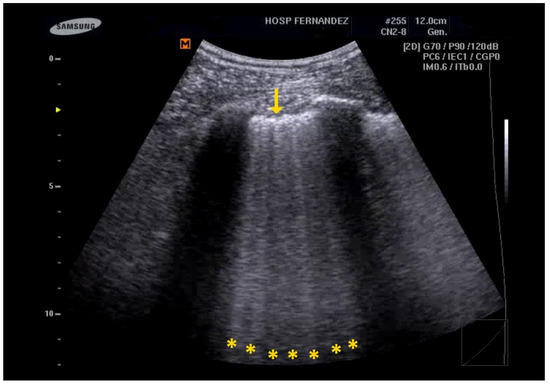

- Multiple B-Lines: These appear in a diffuse, inhomogeneous distribution and are critical for ILD diagnosis.

- Pleural Line Abnormalities: These may include thickening, irregularities, and fragmentation of the pleural line.

5. LUS for the Detection of Consolidations

- Lichtenstein, D.A.; Lascols, N.; Mezière, G.; Gepner, A. Ultrasound diagnosis of alveolar consolidation in the critically ill. Intensive Care Med. 2004, 30, 276–281. [Google Scholar] [CrossRef]